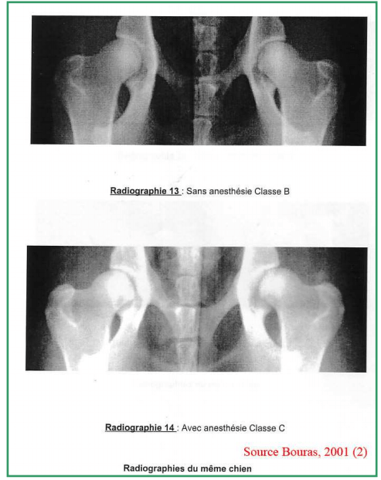

Je dois adopter une petite chienne cocker dans 2 mois. J’ai fait les démarches de réservation en envoyant un chèque qui s’avère être des Arrhes. Aujourd’hui une information supplémentaire s’est ajoutée sur le site de l’élevage concernant la mère des chiots, elle a une dysplasie de type C donc légère. Le père lui est de type B donc presque normal. C’est une maladie qui est héréditaire, par conséquent les chiots ont 50% de chance de présenter cette maladie.